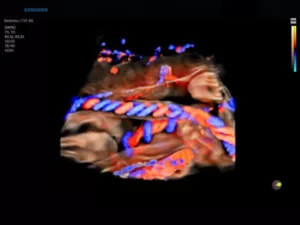

Режим PD (Power Doppler, энергетический)

Является разновидностью ЦДК, однако обладает большей чувствительностью к присутствию кровотока, чем цветовой доплер. Принцип работы PD-сканирования основан на анализе амплитуд всех эхосигналов допплеровского спектра, отражающих плотность эритроцитов в заданном объеме. Оттенки цвета (от темно-оранжевого к желтому) кодируют интенсивность эхосигнала.

Диагностическая ценность энергетической допплерографии состоит в возможности оценки васкуляризации органов и патологических участков. Методика не несет информации о средней скорости кровотока в отдельных элементах изображения, а регистрирует сам факт наличия кровоснабжения.

65.jpg

Рис.6. Плацента, энергетический доплер и 3D-режим.

Режим 3D/4D

Технология объемного сканирования позволяет исследовать пространственное местонахождение объектов в различных проекциях в режиме «замораживания» (3D static) и реального времени (4D). Такая возможность достигается путем совмещения большого количества плоских двумерных изображений, зафиксированных с различных сторон. Наибольшее распространение эхография в 3D и 4D получила в акушерстве и гинекологии.

Для данного типа сканирования применяются объемные датчики. В зависимости от цели обследования излучатели в объемных насадках могут быть линейными, конвексными или фазированными.

66.jpg

Рис.7. Лицо плода в 3D-режиме (объемный датчик 1-8 МГц).